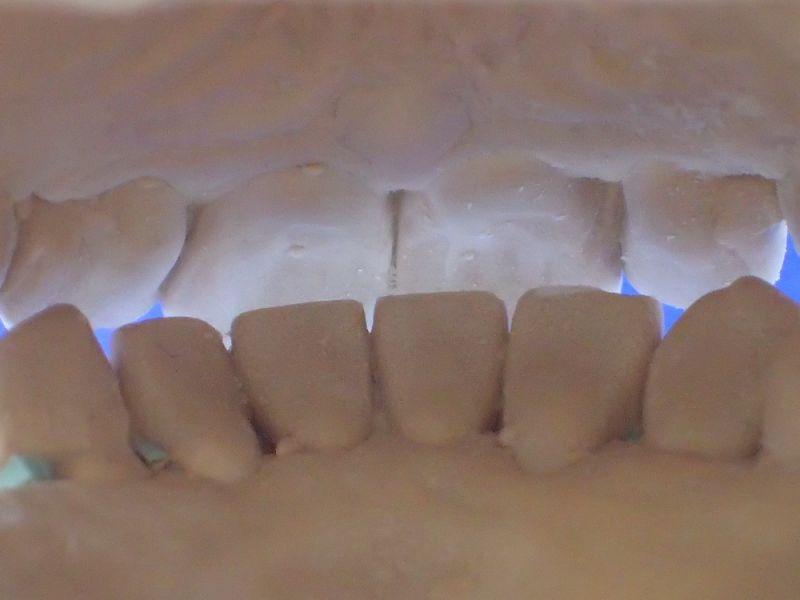

2. Herstellung und Eingliederung eines adjustierten Aufbissbshelfs

Erkennbar ist die massive Abweichung der habituellen Bisslage von der neuromuskulär zentrierten Bisslage.